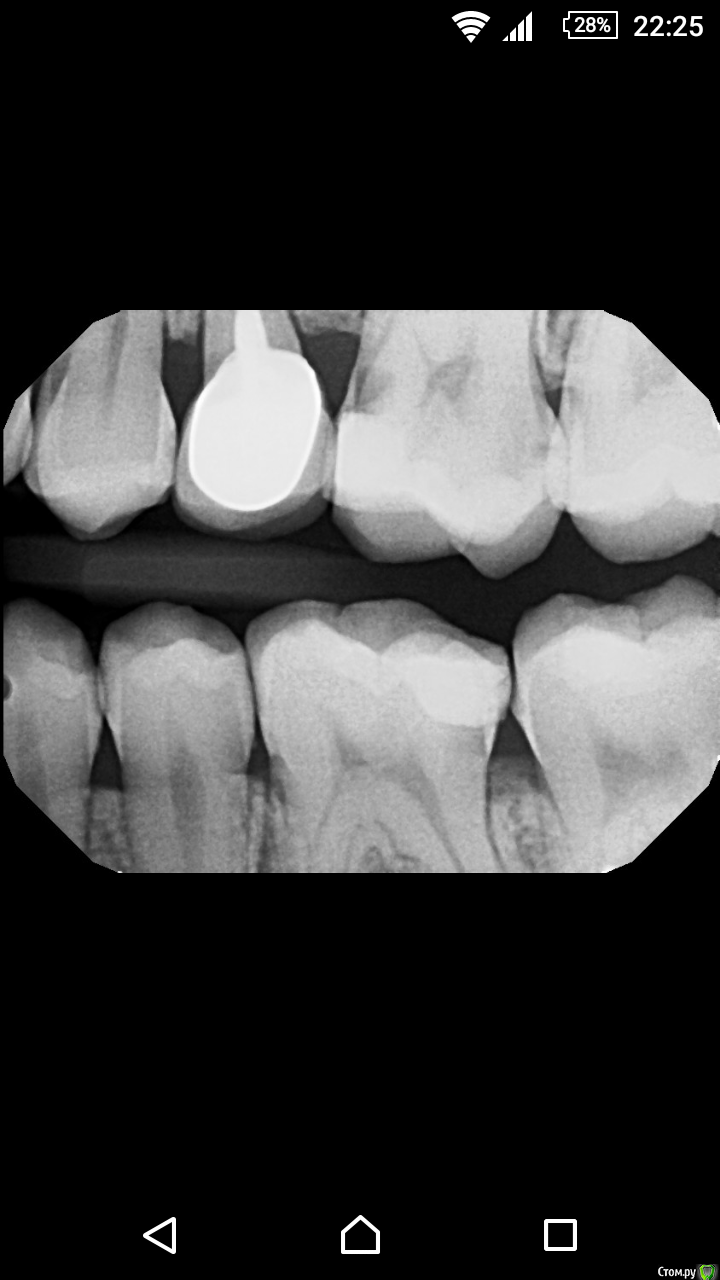

Юлия Сергеевна 85 Опубликовано 18 февраля, 2016 Поделиться Опубликовано 18 февраля, 2016 Коллеги,моей пациентке в Нью Йорке сделали снимки, сказали кариес 4.7 и 2.6.. Сказали коронками обязательно потом покрывать, она хочет сюда прилететь к родственникам и заодно лечить, так как там за все это 3 000 долларов,я вот неуверена по снимкам есть ли там полости. Что скажете? Ссылка на комментарий

ЕленаВалерьевна Опубликовано 19 февраля, 2016 Поделиться Опубликовано 19 февраля, 2016 я тоже думаю что есть. на 4.7 дистально, 2.6 медиально. конечно лучше бы еще во рту посмотреть, прежде чем так однозначно утверждать. да пусть приезжает, и с родными встретится, и если нужно, полечится) Ссылка на комментарий

Zlata-doctor Опубликовано 24 февраля, 2016 Поделиться Опубликовано 24 февраля, 2016 http://s019.radikal.ru/i600/1602/a9/7c45f3051e32.pnghttp://s019.radikal.ru/i618/1602/4d/322cf4914262.png 4.7-как бы не пульпит ( в любом случае контроль через несколько мес после лечения)-полость под экватором и сглажен рог пульпы=раздражена4.6 апроксимальный кариес????4.5-дистальная поверхность??????????1.6 -подозрительная щель в области пломбы медиальной поверхности????2.6 медиальная поверхность под пломбой, дистально возможно, тоже есть ИТОГО2.6 и 4.7 лечение, остальное уточнять, скопировать, или динамическое наблюдение Ссылка на комментарий